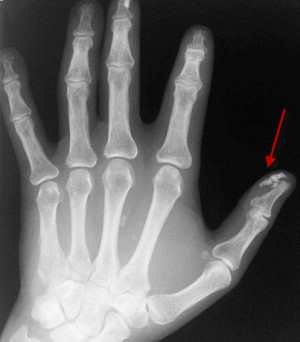

В виду того, что при системной склеродермии история болезни фиксирует поражение множества органов, диагностировать заболевание трудно. Отличительный диагностический симптом – это маскообразность лица со сниженной мимикой и как бы натянутой кожей, а также изменение кистей рук. Они становятся малоподвижные, худые с утолщением концевых фаланг.

- дигитальные рубчики – это западание кожи на фалангах пальцев или уменьшение подушечек пальцев;

- склеродактилия – аналогичные кожные изменения, но ограниченные пальцами;